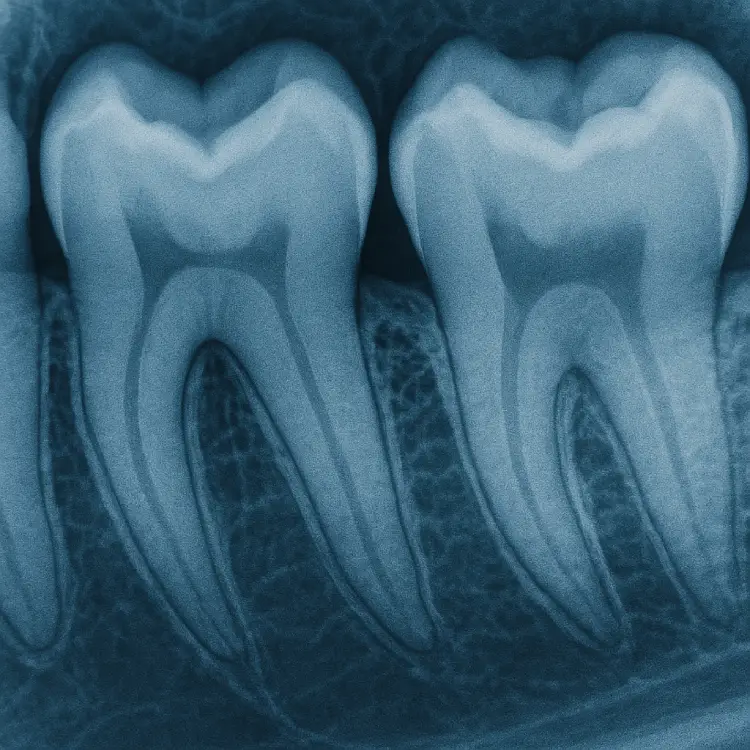

Диагностика

Комплексная диагностика с использованием современного оборудования: рентген, КТ и др. для точной постановки диагноза.